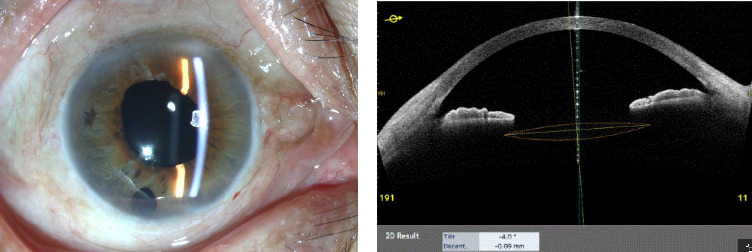

目的:探讨一种改良的无巩膜瓣人工晶状体脱位经巩膜复位的微创技术。方法:本回顾性病例系列包括17眼半脱位或脱位的人工晶状体,采用针内缝合闭环技术重新定位。手术过程包括使用弯曲的30号针将8-0聚丙烯缝线穿过人工晶状体的四个开孔触觉。将外部缝合点埋入巩膜,不造巩膜瓣,不分离结膜。收集和分析术前和术后眼压、最佳矫正视力、人工晶状体位置、角膜内皮细胞计数和术后并发症的数据。随访期至少6个月。结果:17例人工晶状体稳定、中心良好,视力明显改善。随访期间无明显并发症,包括人工晶状体倾斜、脱位、玻璃体出血、低斜视、虹膜捕获或缝线侵蚀。结论:针内缝合闭环技术用于脱位Akreos adaptive人工晶状体经巩膜再固定具有微创性,具有良好的解剖和功能效果,降低了并发症的发生风险。

Purpose: To evaluate a modified minimally invasive technique for trans-scleral repositioning of dislocated Akreos Adapt intraocular lenses (IOLs) without scleral flaps. Methods: This retrospective case series included 17 eyes with subluxated or dislocated IOLs that underwent repositioning using a suture-in-needle, closed-loop technique. The procedure involved passing an 8-0 polypropylene suture through the IOL's four fenestrated haptics using a bent 30-gauge needle. The exterior suture knot was buried into the sclera without creating scleral flaps or dissecting the conjunctiva. Data on pre- and postoperative intraocular pressure, best-corrected visual acuity, IOL position, corneal endothelial cell counts, and intra-/postoperative complications were collected and analyzed. The follow-up period lasted at least 6 months. Results: All 17 cases demonstrated stable and well-centered IOLs with improved visual acuity. No significant complications, including IOL tilt, decentration, vitreous hemorrhage, hypotony, iris capture, or suture erosion, were observed during the follow-up. Conclusion: The suture-in-needle, closed-loop technique for trans-scleral refixation of dislocated Akreos Adapt IOLs is minimally invasive, achieves excellent anatomical and functional outcomes, and reduces the risk of complications.